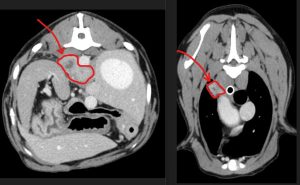

We are lucky at Bridge Referrals to have a fantastic on-site CT scanner, available for 24/7 use. A CT scan showed that Gunner had an abscess in one of his lung lobes and two abscesses behind his diaphragm (around the main arteries into his abdomen!) – shown in red on the below images.

CT images showing an abscess in one of Gunner’s lung lobes and two abscesses behind his diaphragm